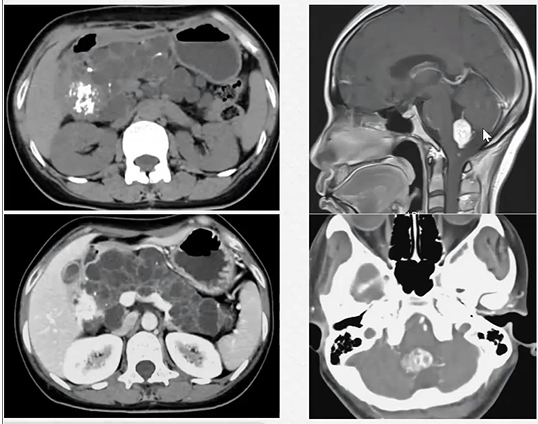

T1WI:实性占位

图5 实性浆液性囊腺瘤(SCN) T1WI显示病灶明显优于T2WI

(图片来源:余日胜教授讲课使用)

02

T2WI:囊性占位及纤维分隔

图6 胰腺囊性病灶及纤维分隔:T2WI